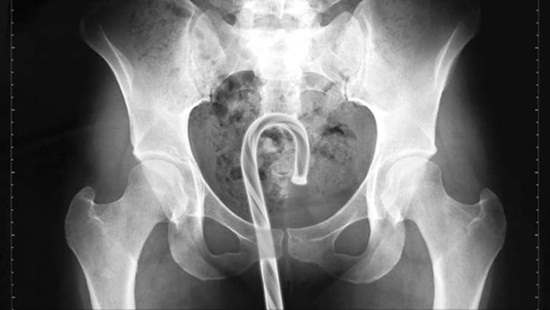

มาดูภาพเอกซเรย์ สารพัดสิ่งของที่เคยหลุดเข้าทวารหนัก

เผยภาพเอกซเรย์สุดอึ้ง สารพัดสิ่งที่เคยหลุดเข้าไปภายในทวารหนักผู้ป่วยทั่วโลก แปลกพิสดารกันจริง ๆ

การยัดสิ่งของต่าง ๆ เข้าไปในทวารหนักนั้น ไม่ว่าจะด้วยเหตุผลเพื่อหลบซ่อนการตรวจของเจ้าหน้าที่ทางการ หรือเป็นความผิดพลาดจากการแก้ขัดเมื่อเกิดอารมณ์ทางเพศก็ตาม สิ่งของที่หลุดเข้าไปนั้นล้วนแล้วแต่สร้างอันตรายให้กับอวัยวะภายในของผู้ป่วยได้หมด แต่ถึงจะเป็นอย่างนั้น เคสทางการแพทย์ว่าด้วยเรื่องของสิ่งแปลกปลอมที่หลุดเข้าไปในทวารหนักก็ยังมีให้เห็นอยู่เรื่อย ๆ ถมเถ แต่ละอย่างทำเอาอึ้ง ทึ่ง แบบไม่คิดว่ามันจะหลุดเข้าไปในทวารหนักได้จริง ๆ ดังเช่นตัวอย่างเคสที่เรานำมาฝากกันในวันนี้..

แคนดี้เคน

กระป๋องสเปรย์